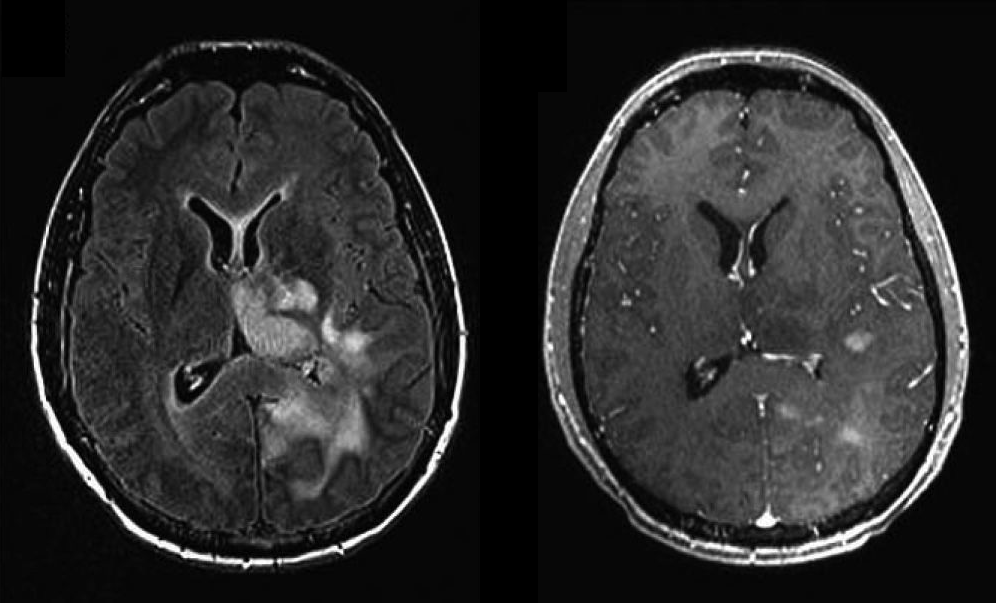

resonancia de un caso de gliomatosis cerebri con varios tumores

La resonancia magnética y el escáner o tomografía computerizada (TAC) son las pruebas radiológicas más importantes que se llevan a cabo para la detección de esta enfermedad.

Al realizar las pruebas de imagen se inyecta contraste para teñir las células tumorales para que se puedan distinguir fácilmente y que el radiólogo pueda distinguir entre el tejido sano y el canceroso.